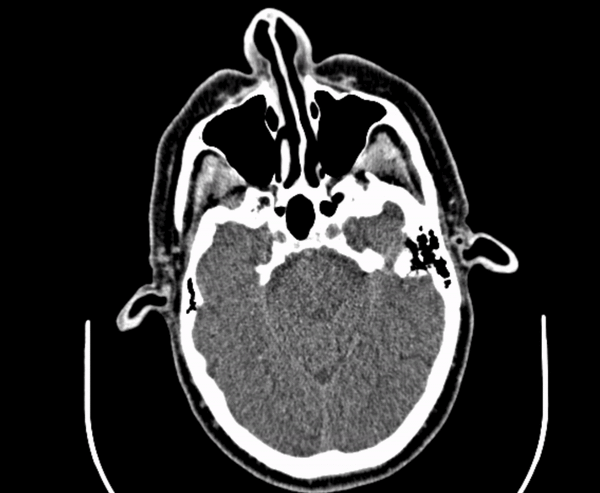

If a picture is worth 1000 words, how many words is a DICOM?

A tool for interactive case presentations